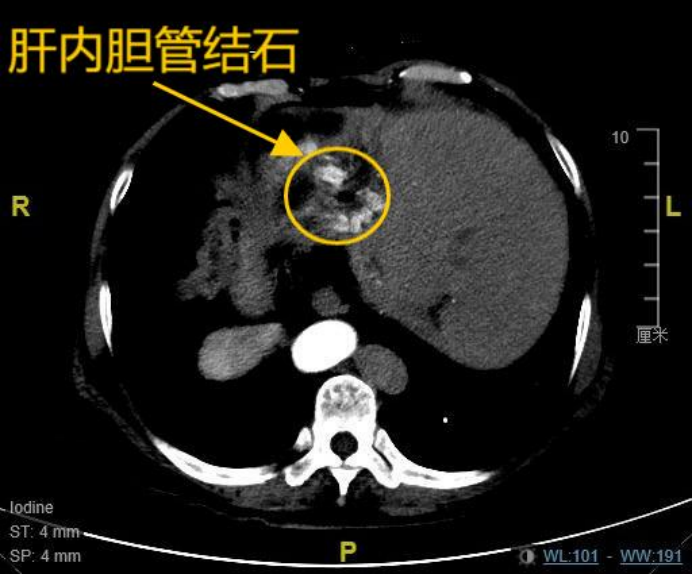

患者韩女士(化名),67岁,8年前因胆总管结石、胆囊结石曾接受传统开腹手术,术后三年结石复发,导致其长期饱受肝内胆管结石困扰,反复发作的右上腹疼痛严重影响了她的生活质量。更为特殊的是,韩女士存在罕见的全内脏反位,即医学上所指的“镜面人”,她的心脏、肝脏、脾脏等脏器均与正常解剖位置呈镜像反位分布,这是一种罕见的内脏解剖变异,发生概率约万分之一,这为手术操作带来极大挑战。8年前,由于特殊的身体情况,其开腹手术曾耗时长达10小时。近期复查的肝胆CT提示:肝内胆管多发结石伴肝左叶萎缩,肝总管及部分二级胆管扩张。面对多家医院“需再次开腹”的诊疗建议,患者坚持寻求微创解决方案,最终慕名求诊于哈医大一院肝脏微创外科麻勇主任团队。